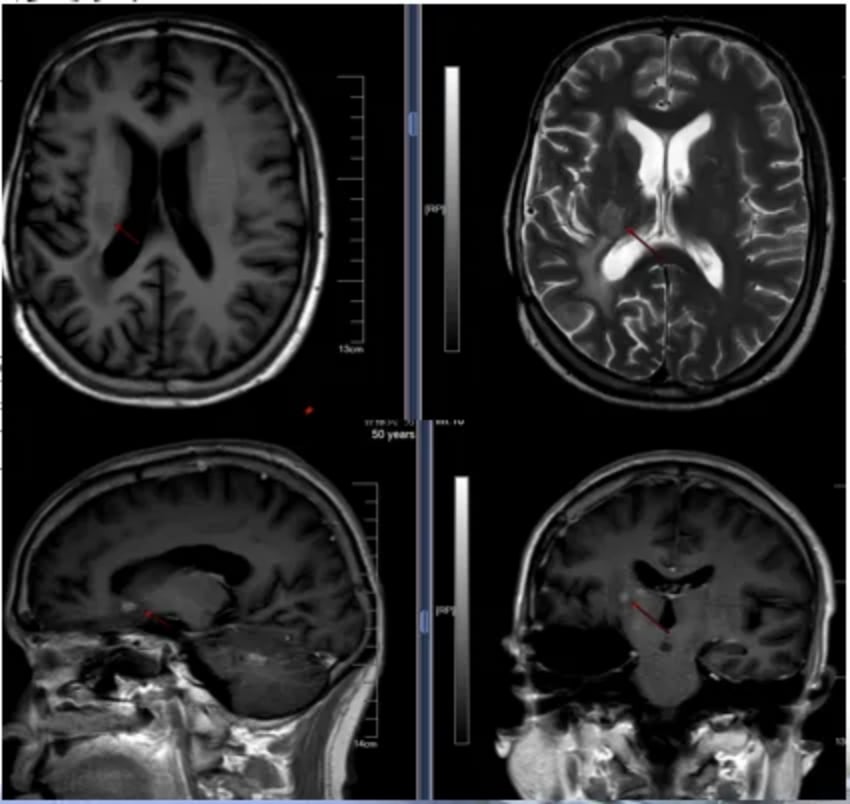

尽管后续MRI显示脑内仍有微小病灶进展,但得益于前期有效的联合治疗和后续的替尼泊苷维持治疗,患者的无进展生存期得到了显著延长。对于需要长期用药的患者,获取稳定可靠的药物来源至关重要。MedFind致力于为癌症患者提供专业的海外靶向药和化疗药代购服务,确保治疗的连续性。

图9 后续随访MRI图像

本例患者从初诊到最近一次随访,整个诊疗过程体现了高级别胶质瘤治疗的长期性和复杂性。初始的标准Stupp方案后,患者的无进展生存期(PFS1)达到了18个月。在首次复发后,采用替尼泊苷联合贝伐珠单抗的创新方案,成功将二次无进展生存期(PFS2)延长至24个月,极大地延缓了病情进展,为患者争取了宝贵的生命时间。